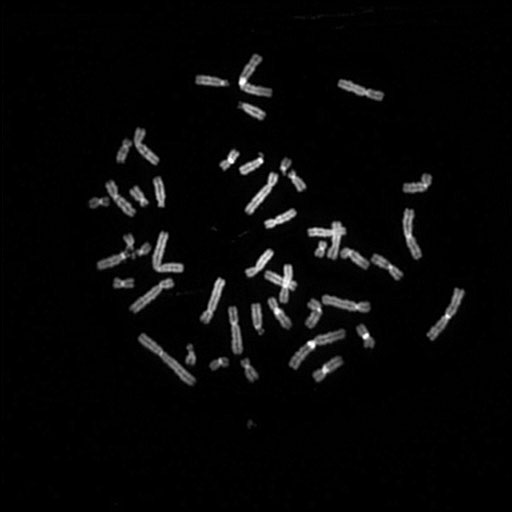

081 M

081 C

081 D